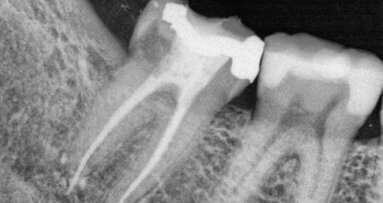

KODAŇ, Dánsko: Řada nedávných studií ukázala, že zubní kameny z archeologických vzorků by mohly být bohatým zdrojem pro lepší pochopení zubního zdraví našich předků. Podobně pak nová studie zubního kamene z ostatků pohřbených na dánském hřbitově vrhla světlo na orální mikrobiomy určitých skupin středověkých obyvatel v této oblasti.

Tým z Kodaňské univerzity vedl studii a porovnával vzorky zubního kamene z ostatků 21 lidí pohřbených přibližně mezi lety 1100-1450 na středověkém hřbitově vesnice Tjærby v Dánsku. Ze zubního kamene bylo identifikováno celkem 3 671 proteinů z 220 různých proteinových skupin, přičemž přibližně 85 až 95 % bylo vyrobeno bakteriemi z orálního mikrobiomu.

Ačkoli všechny studované vzorky vykazovaly stopy bakterií spojených s periodontálním onemocněním a zubním kazem, výzkumný tým rozdělil vzorky do dvou skupin: jedné, která měla predispozice k dobrému zdraví a druhé náchylnější k orálnímu onemocnění. V první skupině došlo pouze k jednomu případu periodontitidy, zatímco sedm členů druhé skupiny vykazovalo známky závažného zubního kazu. Přestože je více než pravděpodobné, že tyto dvě skupiny jedly podobnou stravu a měly shodné návyky v péči o orální zdraví, rozdíl ve výsledcích orálního zdraví lze nejspíše přisuzovat rozdílům v bílkovinách, odkazujících na přítomnost Streptococcus sanguinis, relativně neškodné bakterie, které byly mnohem častější v orálním mikrobiomu pacientů z první skupiny.

Navzdory těmto rozdílům bylo zjištěno, že použité vzorky zubního kamene jsou mnohem heterogennější než vzorky získané od současných dánských jedinců. Autoři studie se domnívají, že hlavními příčinami této rozmanitosti v mikrobiomech současných obyvatel bude pravděpodobně větší rozmanitost moderní stravy, v kombinaci s faktory životního prostředí a životního stylu, genetiky, hygienických postupů a různé četnosti užívání antibiotik u jednotlivých osob.

Studie pod názvem “Quantitative metaproteomics of medieval dental calculus reveals individual oral health status” („Kvantitativní meta proteomika středověkého zubního kamene odhaluje individuální stav orálního zdraví“), byla publikována online v časopise Nature Communications dne 20. listopadu 2018.